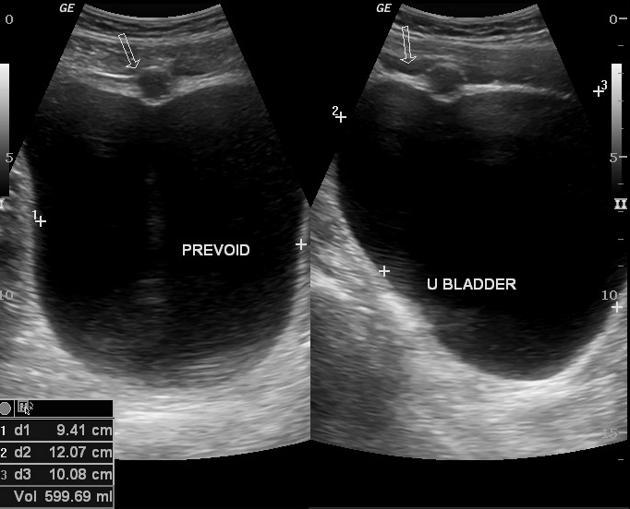

Ureteroceles

Transitional Cell Carcinoma

Most common bladder neoplasm

hematuria

hydronephrosis

Transitional Cell Carcinoma